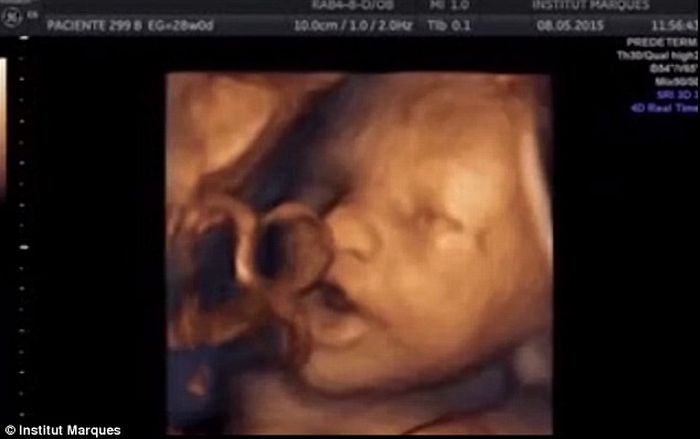

Στο πείραμα μετείχαν έγκυες γυναίκες που διένυαν από την 14η έως την 39η εβδομάδα της κύησης. Κατά τη διάρκεια της μελέτης, η ομάδα χρησιμοποίησε υπέρηχο, για να παρακολουθήσει τις αντιδράσεις των εμβρύων στο άκουσμα της μουσικής. Η μετάδοση της μουσικής έγινε με αναπαραγωγή τόσο κοντά στην κοιλιά της μέλλουσας μητέρας όσο και ενδοκολπικά με ειδικό ηχείο μικρού μεγέθους εντός του κόλπου.

Όταν τα μωρά «εκτέθηκαν» στη μουσική (ενδοκολπικά), το συντριπτικό 87% ανταποκρίθηκε κουνώντας το κεφάλι και τα άκρα μαζί. Οι κινήσεις αυτές συνοδεύονταν μάλιστα από συγκεκριμένες κινήσεις του στόματος και της γλώσσας, οι οποίες σταματούσαν όταν σταματούσε και η μουσική. Επιπλέον, το 50% των εμβρύων ανταποκρίθηκε στη μουσική με μια πολύ έντονη κίνηση: άνοιξαν διάπλατα το σαγόνι τους και έβγαλαν έξω τη γλώσσα τους όσο περισσότερο μπορούσαν.